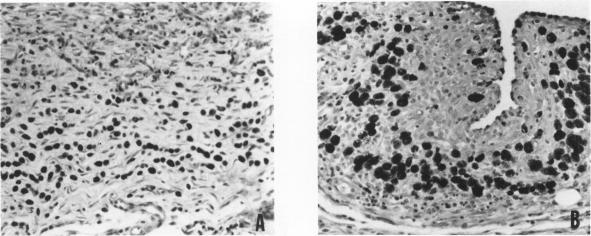

Injection of streptococcus group A cell wall-derived peptidoglycan polysaccharide into a subcutaneous air pouch causes local outpouring of neutrophils and macrophages and distant hemopoietic proliferation in spleen and bone marrow. Cyclosporine A (CyA) suppressed neutrophil accumulation and all cell lines of hemopoiesis. trans-1,2-Bis(5-amidino-2-benzimidazolyl)ethene (BBE) also interfered with neutrophil exudation, yet reduced only the erythroid component of the hemopoietic process. The ethane analogue of BBE, on the other hand, did not prevent neutrophil emigration, but held down splenic erythropoiesis and myelopoiesis. All three compounds stimulated streptococcus group A cell wall-derived peptidoglycan polysaccharide uptake by pouch macrophages. CyA being the least active, BBE and its ethane analogue also produced a shift of wear-and-tear pigment from large numbers of small splenic macro-phages into small numbers of large macrophages. The pouch model is very useful in the study of anti-inflammatory compounds and has furnished the first evidence of CyA interference with massive neutrophilic infiltration and with hemopoietic signals.

将A组链球菌细胞壁衍生的肽聚糖多糖注射到皮下气囊中会导致中性粒细胞和巨噬细胞在局部渗出,并使脾脏和骨髓出现远处造血增殖。环孢素A(CyA)抑制中性粒细胞聚集以及所有造血细胞系。反式-1,2-双(5-脒基-2-苯并咪唑基)乙烯(BBE)也干扰中性粒细胞渗出,但仅减少造血过程中的红系成分。另一方面,BBE的乙烷类似物并未阻止中性粒细胞迁移,但抑制了脾脏的红细胞生成和骨髓生成。这三种化合物均刺激气囊巨噬细胞摄取A组链球菌细胞壁衍生的肽聚糖多糖。CyA活性最低,BBE及其乙烷类似物还使大量小脾脏巨噬细胞中的损耗色素转移到少量大巨噬细胞中。气囊模型在抗炎化合物研究中非常有用,并且提供了CyA干扰大量中性粒细胞浸润和造血信号的首个证据。